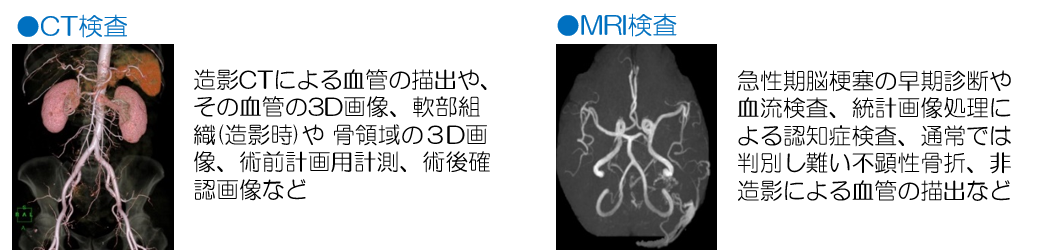

当科の検査装置は、CT(64列)、MRI(1.5T)、核医学診断装置、全身用骨密度測定装置(DXA)、血管造影装置、X線透視装置、X線撮影装置、ポータブル装置、外科用イメージ装置、ワークステーション装置から構成されております。

これらの検査装置を駆使して、一般的な検査内容はもちろんの事、これらと共に、以下に示すような業務内容も行っております。